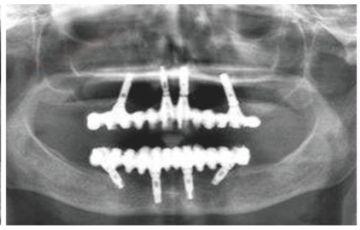

種植修復(fù)后X光片

這一位老先生則選擇了All-on-4種植技術(shù),即拔即種,上下頜分別種植4個(gè)植體就完成了全口牙齒修復(fù),費(fèi)用降低了不少,而且創(chuàng)傷小,恢復(fù)快。